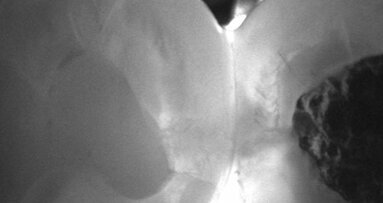

LEIPZIG – Die Nahinfrarot-Transillumination ist am 13. Mai Thema eines Webinars, das der DT Study Club anbietet. Im Rahmen der kostenfreien ...